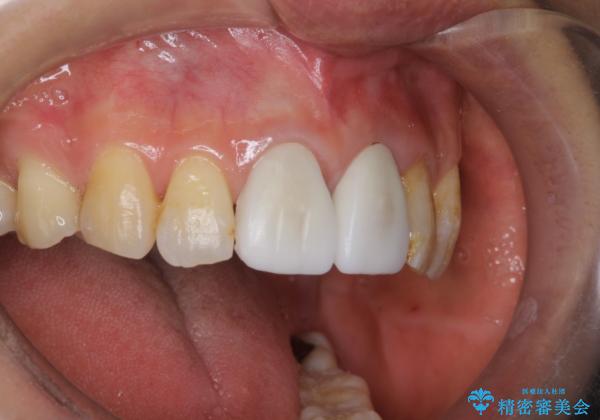

変色した前歯をセラミックできれいに レイヤリングセラミック

前歯のセラミック治療では、他の歯と色調をそろえるのが非常に難しいです。

他の歯に亀裂や白濁など複雑な色合いがある場合、それらをセラミックで再現することも可能ですが、スタンダードのオールセラミックではある程度の同調となります。

かぶせ物の種類: PFZ standard